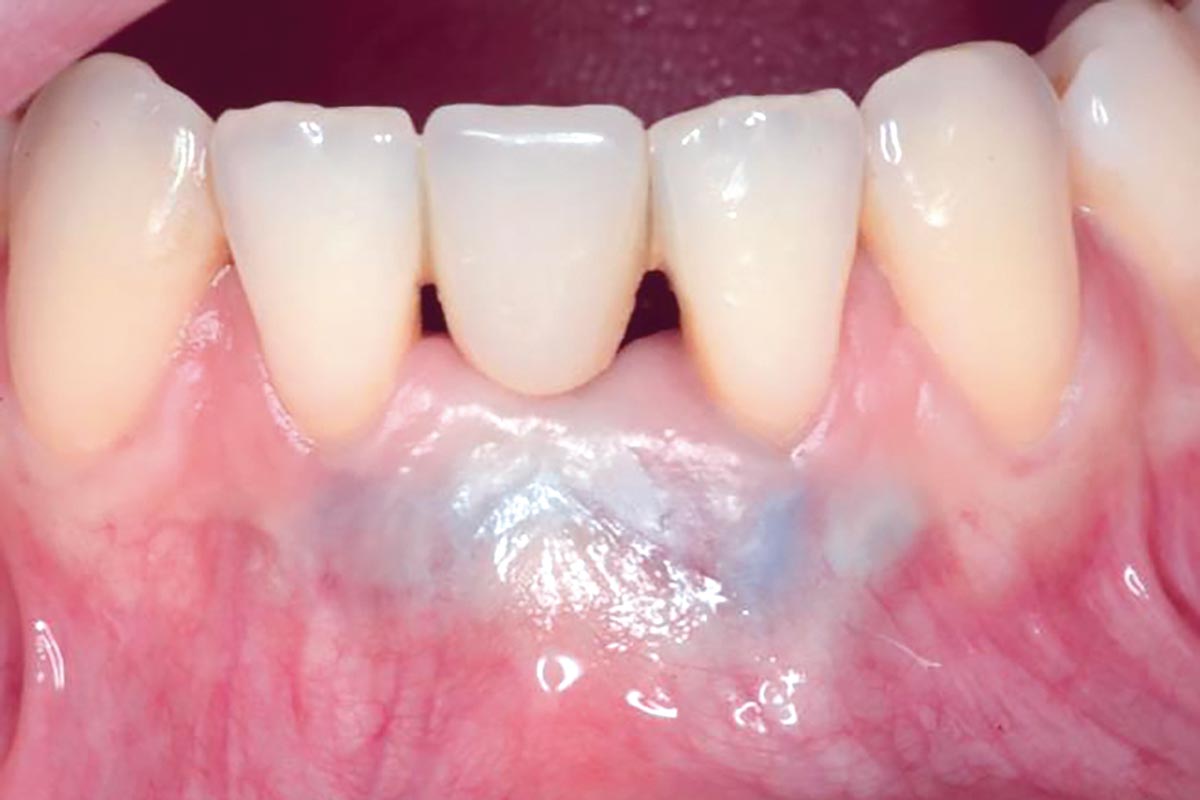

Regenerative corticotomy to compensate lower incisor malocclusion with cerabone® and mucoderm®

Initial view of the clinical case: Class III malocclusion

Treatment plan: Regenerative corticotomy (PAOO)